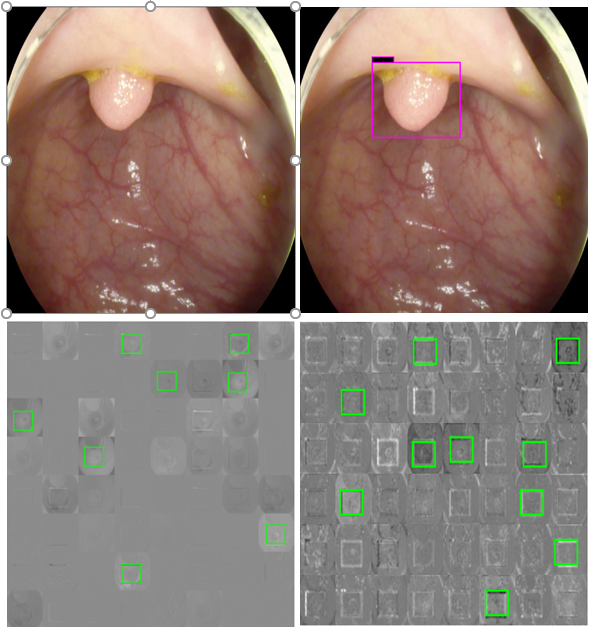

For single and deep layer of the proposed model, we have shown channel activation representing the convolutional kernels accurately detected the polyp. Fig. 7 shows different bright and dark parts corresponding to the spatial property of the object within the test images for single and deep layers. The top left is the test polyp image followed by top right detection output generated by proposed deep CNN model. The bottom left shows the single layer activation channel whole bottom right shows the deep layer for deeper feature analysis represented by green rectangular boxes. It can be observed in Fig. 7, that both single and deep layers are extracting polyp features with a high score, resulting in high polyp detection.